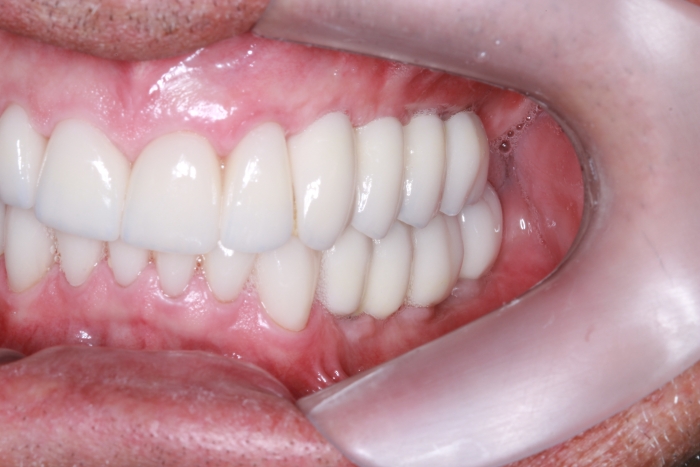

Intra oral direita final

Intra oral esquerda final